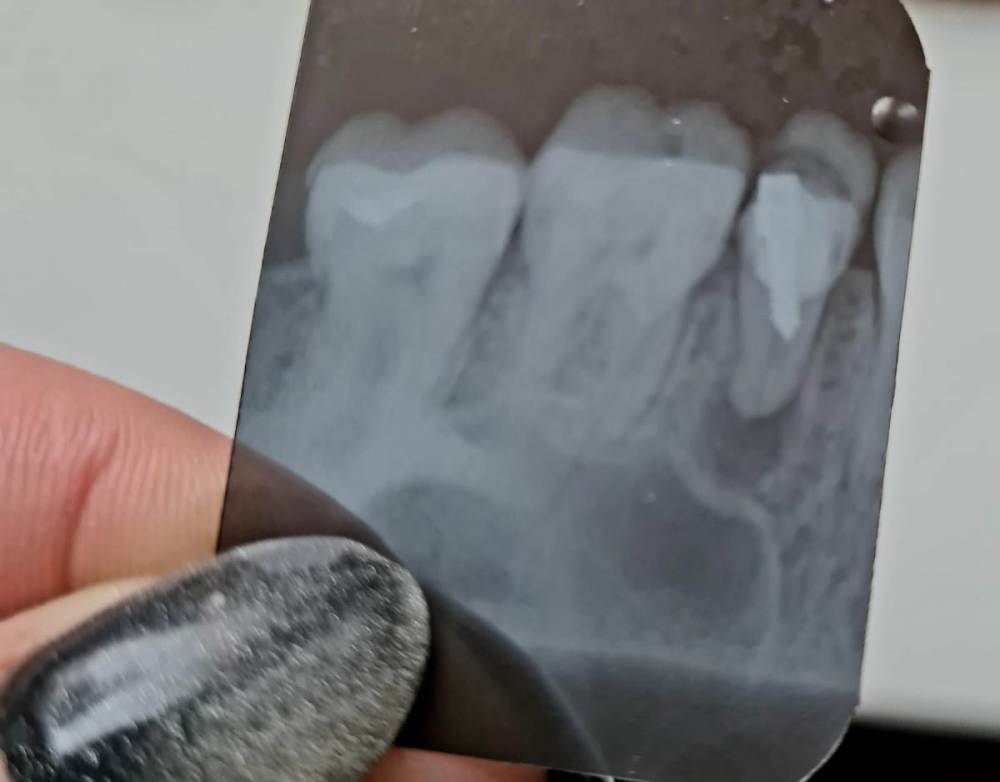

Ольга 777 Опубликовано 23 января, 2023 Поделиться Опубликовано 23 января, 2023 (изменено) Здравствуйте! Есть киста на зубе. Стоит штрифт . Сейчас опухла щека и болит поллица. Удалять зуб жалко. Есть ли шанс сохранить зуб.? Изменено 23 января, 2023 пользователем Ольга 777 Ссылка на комментарий

red_butler Опубликовано 23 января, 2023 Поделиться Опубликовано 23 января, 2023 Здравствуйте. Если судить только по снимку, то удалять. 1 Ссылка на комментарий

Ольга 777 Опубликовано 23 января, 2023 Автор Поделиться Опубликовано 23 января, 2023 (изменено) Я правильно поняла: канал был запломбирован не полностью и штифт давит на стенку канала. Может быть в этом причина возникновения кисты? Изменено 23 января, 2023 пользователем Ольга 777 Ссылка на комментарий

red_butler Опубликовано 23 января, 2023 Поделиться Опубликовано 23 января, 2023 12 минут назад, Ольга 777 сказал: Я правильно поняла: канал был запломбирован не полностью и штифт давит на стенку канала. Может быть в этом причина возникновения кисты? Только по одному снимку ответить не возможно, по снимку зуб сильно разрушен и скорее всего не возможно его восстановить коронкой. 1 Ссылка на комментарий